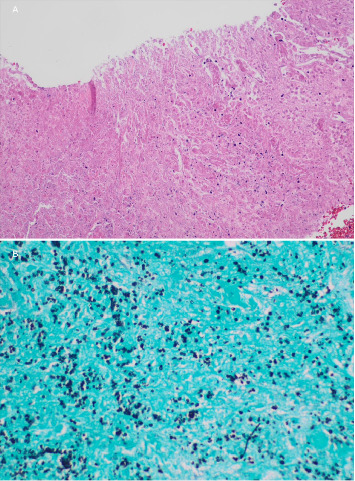

组织胞浆菌病是一种由真菌荚膜组织胞浆菌引起的真菌感染,很少出现中枢神经系统(CNS)表现,包括脑膜炎、脑炎、局灶性脑或脊髓病变以及中风综合征。由于患者之间的差异,中枢神经系统组织浆菌病是一种难以进行临床诊断的疾病,而没有高灵敏度的诊断测试则进一步阻碍了诊断。在这里,我们提出一个独特的案例,46岁的男性免疫功能低下,由于1型糖尿病和弥散性组织胞浆菌病作为脊髓病的急性表现。患者在就诊前几天左腿无力,神经学检查显示有急性胸椎脊髓病的迹象,特别是与布朗-萨默综合征有关。核磁共振成像显示胸脊髓强化病灶,同时伴有多发脑强化病灶,双侧肾上腺肿块和无数肺结节。活检结果显示酵母形式与组织浆菌种类一致。

Histoplasmosis is a fungal infection caused by the fungus Histoplasma capsulatum that can rarely present with central nervous system (CNS) manifestations that include meningitis, encephalitis, focal brain or spinal cord lesions, and stroke syndromes. Because of this variation from patient to patient, CNS histoplasmosis is a difficult clinical diagnosis to make, which can be further hindered by no highly sensitive diagnostic testing available. Here, we present a unique case of a 46-year-old male immunocompromised due to type 1 diabetes mellitus with disseminated histoplasmosis as an acute presentation of myelopathy. Patient had left leg weakness for a few days prior to presentation and a neurological exam remarkable for signs of acute thoracic myelopathy, specifically concerning for Brown-Séquard syndrome. MRI imaging demonstrated an enhancing thoracic spinal cord lesion along with multiple cerebral enhancing lesions, bilateral adrenal masses, and innumerable pulmonary nodules. Biopsy results demonstrated yeast forms consistent with Histoplasma species.